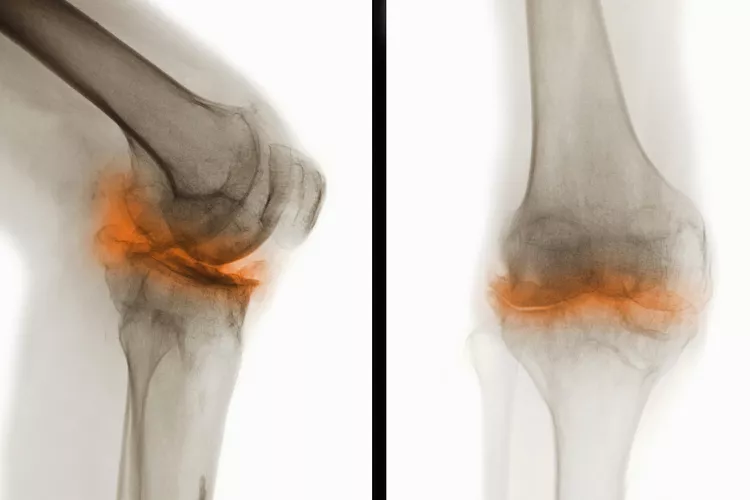

骨關(guān)節(jié)炎(Osteoarthritis, OA),一種常見的慢性關(guān)節(jié)疾病,主要特征是關(guān)節(jié)軟骨退化和關(guān)節(jié)邊緣骨質(zhì)增生。隨著病情進(jìn)展,骨關(guān)節(jié)炎不僅會導(dǎo)致關(guān)節(jié)疼痛和功能受限,還可能引發(fā)一系列并發(fā)癥,影響患者的整體健康和生活質(zhì)量。

在骨關(guān)節(jié)炎(OA) 中,覆蓋骨頭末端并幫助骨頭相互滑動的光滑軟骨會逐漸磨損。這會導(dǎo)致骨頭相互摩擦和磨擦。

骨關(guān)節(jié)炎是一種慢性疾病。骨關(guān)節(jié)炎無法治愈。一旦軟骨破裂,它就不會自行再生。隨著時間的推移,您可能會因患有骨關(guān)節(jié)炎而出現(xiàn)其他問題或并發(fā)癥。